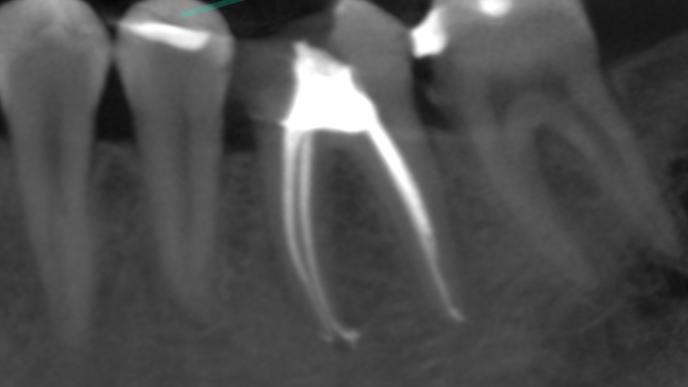

Na poniższych zdjęciach RTG – WIDAĆ GOJENIE ZMIAN ZAPALNYCH KOŚCI.

Leczenie kanałowe jest leczeniem skutecznym. Prawidłowe leczenie kanałowe sprawia, że ząb przestaje być ogniskiem zakażenia, a tkanki wokół goją się. Wyleczenie zęba powoduje, że przyczyna choroby tkanek około zębowych [na RTG widzimy jedynie chorobę kości] zostaje usunięta. Eliminacja przyczyny choroby umożliwia gojenie się zmian chorobowych.